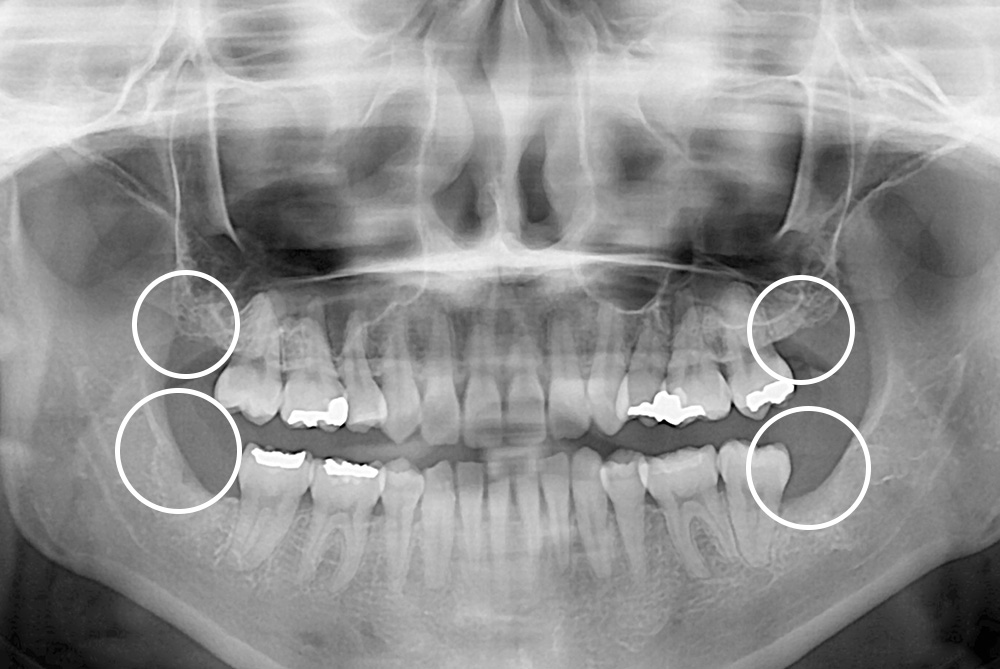

[사랑니] 매복 사랑니 발치

치료후 : 2019-11-11

세종치과는 구강악안면외과학 박사이신 원장님이 발치하는 치과입니다.